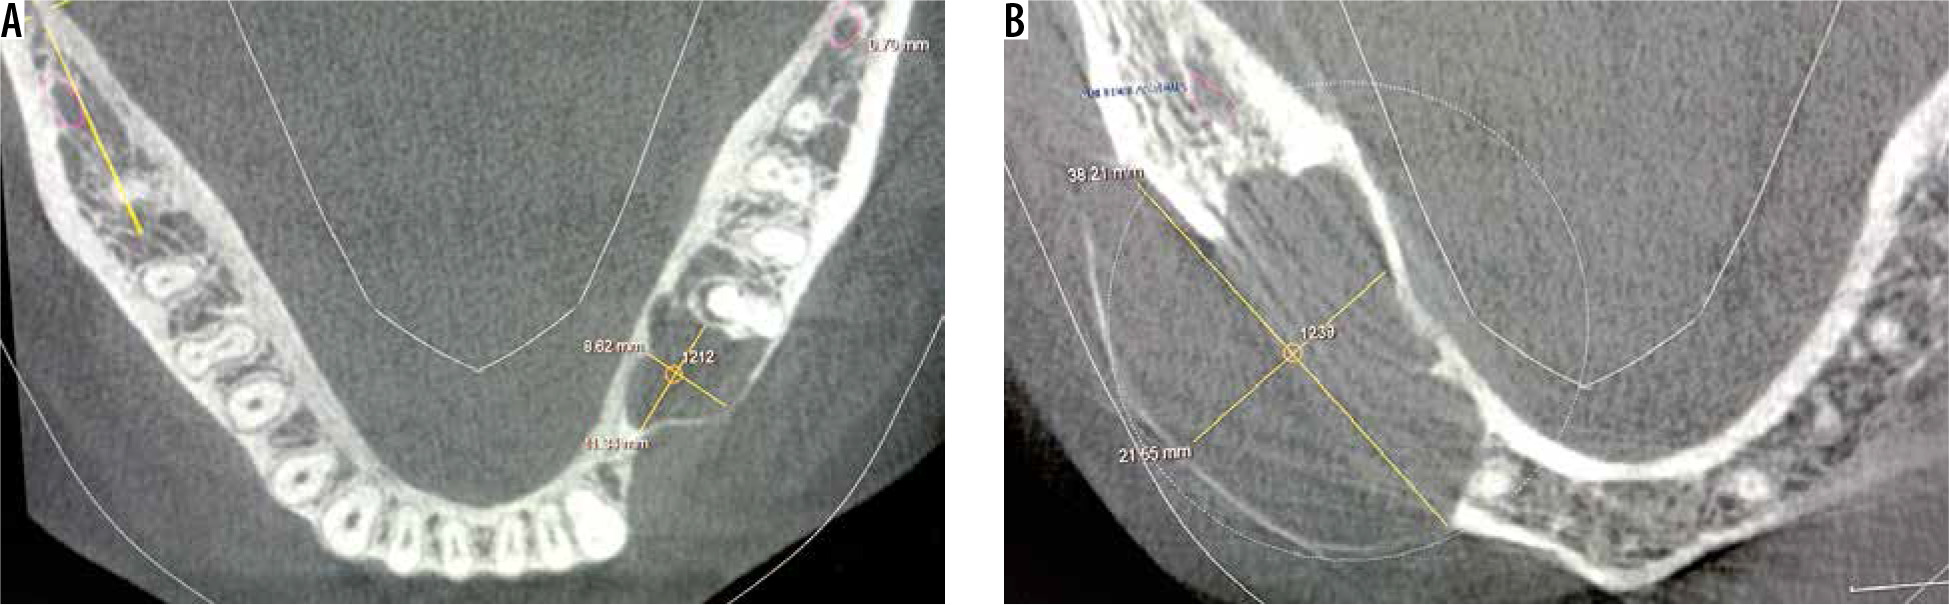

The greyscale measurements were done on axial section of CBCT. For analysis of the grey values, the epicentre of the lesion was evaluated. The intersection of two perpendicular lines at the centre of the lesion was considered as the epicentre, as shown in Figure 1.

Figure 1

Cone beam computed tomography scan showing axial sections of two benign osseous lesions for the measurement of grey scale value at the epicentre of the lesion